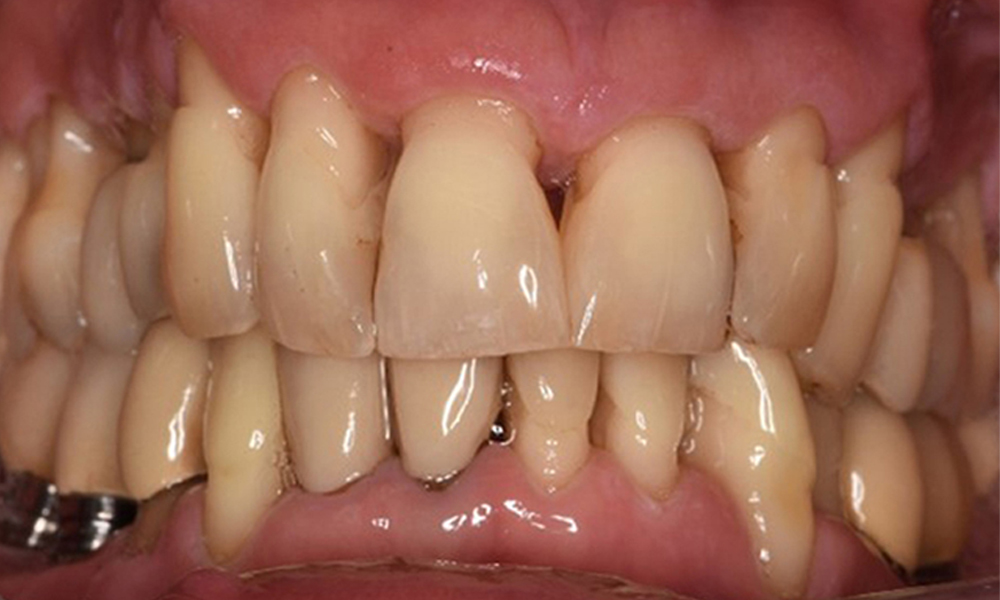

A 52-year-old patient presents at a preventive care session. The patient has no systemic disease and is not taking any medication. He has had various dental treatments and also has two active carious lesions. In addition, the patient has four implants (2nd, 3rd and 4th quadrants). He is revealed to have early periodontal disease (stage IV, grade B). His periodontal condition is stable; a probing depth of Probing depths (ST) of 5 mm is only evident at the implant in region 36. Gingivitis is also identified.

The patient has no particular risk factors with specific dental implications in his medical history. The key factor, therefore, is the requirement in terms of oral health. In this respect, there is evidence of a probing depth of 5 mm at the implant in the 3rd quadrant and, on the X-ray image, increased bone loss. The patient also has currently stable early periodontal disease and two active initial carious lesions.

Oral hygiene and patient compliance are very good (see picture “front view”). All that is required is repeat instruction and motivation to maintain oral hygiene behaviour.